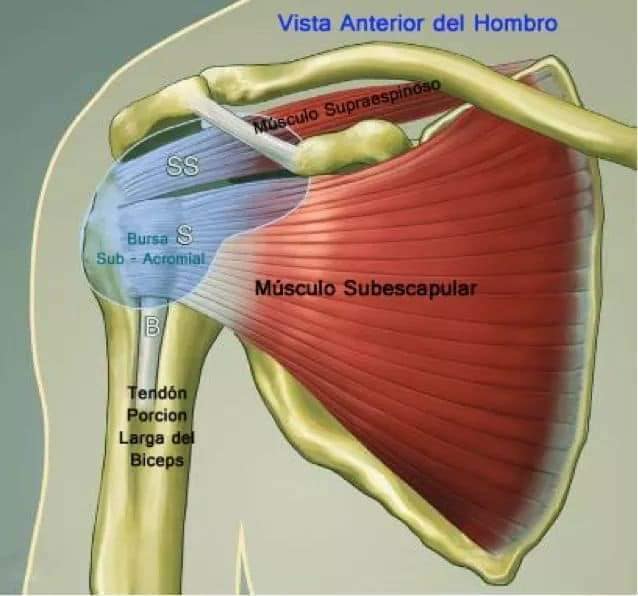

Спинні м'язи

Спинні м'язи виконують функції підтримки хребта, а також дозволяють здійснювати рухи тулуба.

Поверхневі спинні м'язи

М'язи, що піднімають лопатку: Трапецієподібний м'яз: великий м'яз, що покриває верхню частину спини. Його функція - підтримка і рух лопаток, а також забезпечення стабільності хребта.

М'язи, що ведуть лопатку до хребта: Широкий м'яз спини: великий м'яз, що розташований в нижній частині спини. Він відповідає за рухи плечей і лопаток, а також за розширення верхньої частини тулуба.